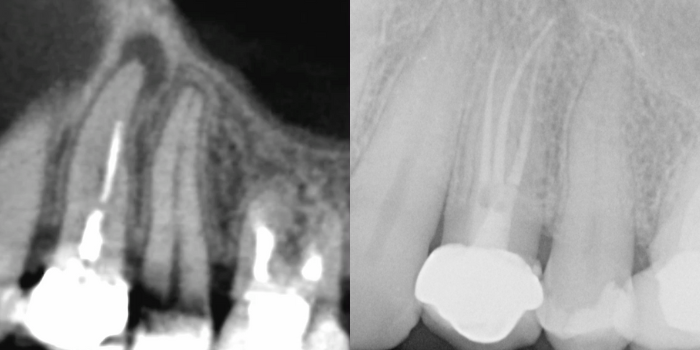

The patient first visited the clinic in 2017 with concerns about the possibility of retreatment for teeth 26 and 24. At that time, it was decided to retreat tooth 26 due to the presence of symptomatic apical periodontitis. Tooth 24, despite a questionable obturation, showed no signs or symptoms of pathology, so periodic radiographic monitoring was chosen.

After four years of follow-up, a radiolucent image was observed at the periapical level of tooth 24, although the patient remained asymptomatic. A CBCT (Cone Beam Computed Tomography) was performed to evaluate the size of the lesion, confirming the presence of asymptomatic apical periodontitis and the need for non-surgical retreatment.